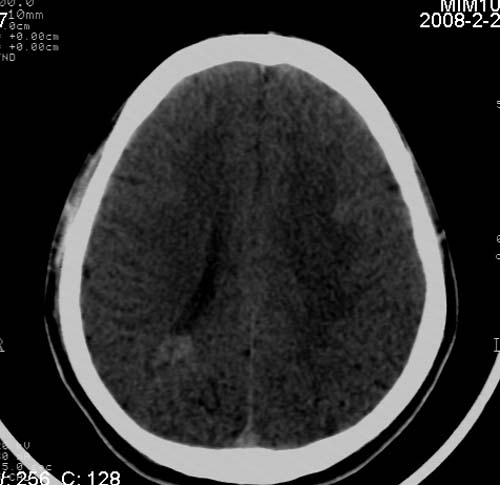

男,17岁,3天前与人斗殴,自述头痛、头晕。无恶心、呕吐,无阳性体征,一般情况良好。

病灶以钙化为主,无明显占位效应,病灶周围无水肿,这种情况应该是脑血管畸形,最多见的是动静脉畸形,其次是海绵状血管瘤.

考虑为:右侧顶叶脑血管畸形。建议:行进一步检查明确诊断。

病人较年轻,有头疼、头晕症状,动静脉畸形可能性大。